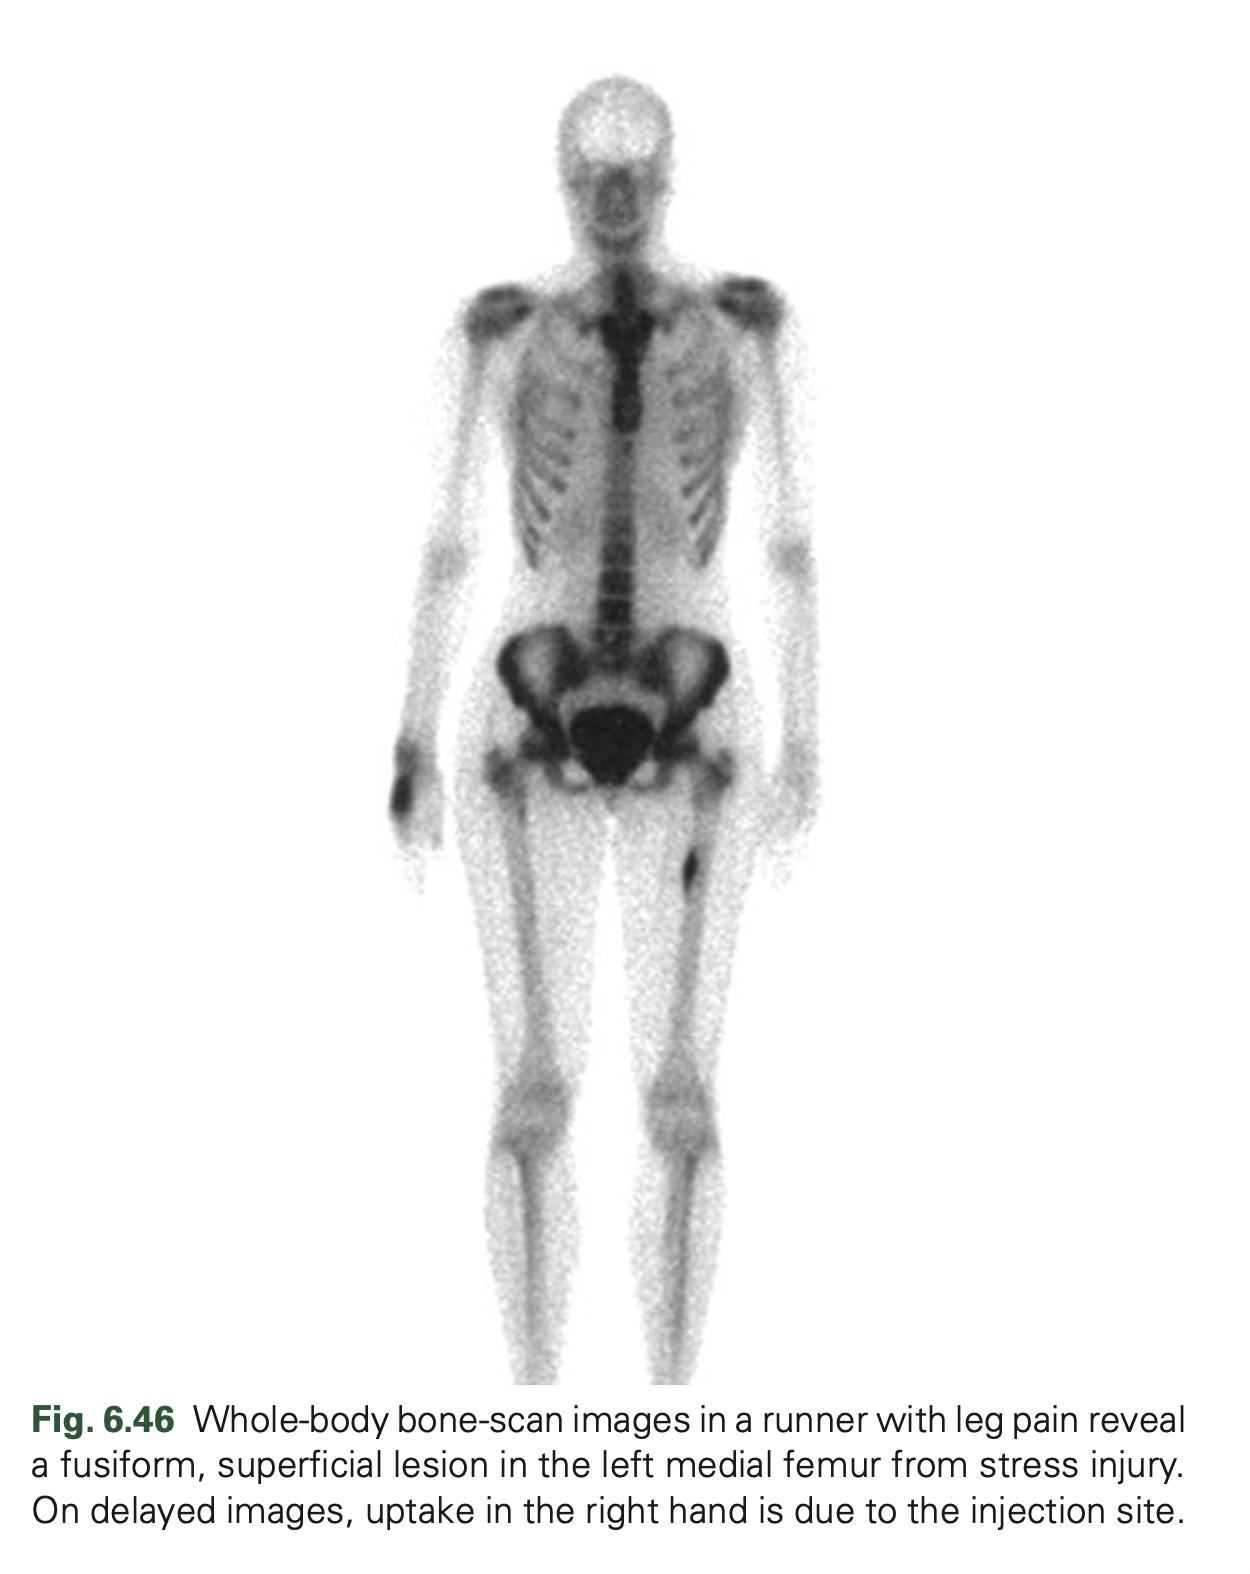

Shin splints and stress fractures often get categorized as the same thing, panchal said, explaining that the main differences are that, while shin splints are caused by. Stress fracture should be suspected in persons with a drastic recent increase in physical activity or repeated excessive activity with limited rest. Mri is the most sensitive modality for detecting stress fracture, and may also be useful for differentiating ligamentous/cartilaginous injury from a bony injury.

36, 51 scintigraphy is able. Most stress fractures are caused by. One or more of the following diagnostic imaging exams may be used to confirm the presence of a foot stress fracture.